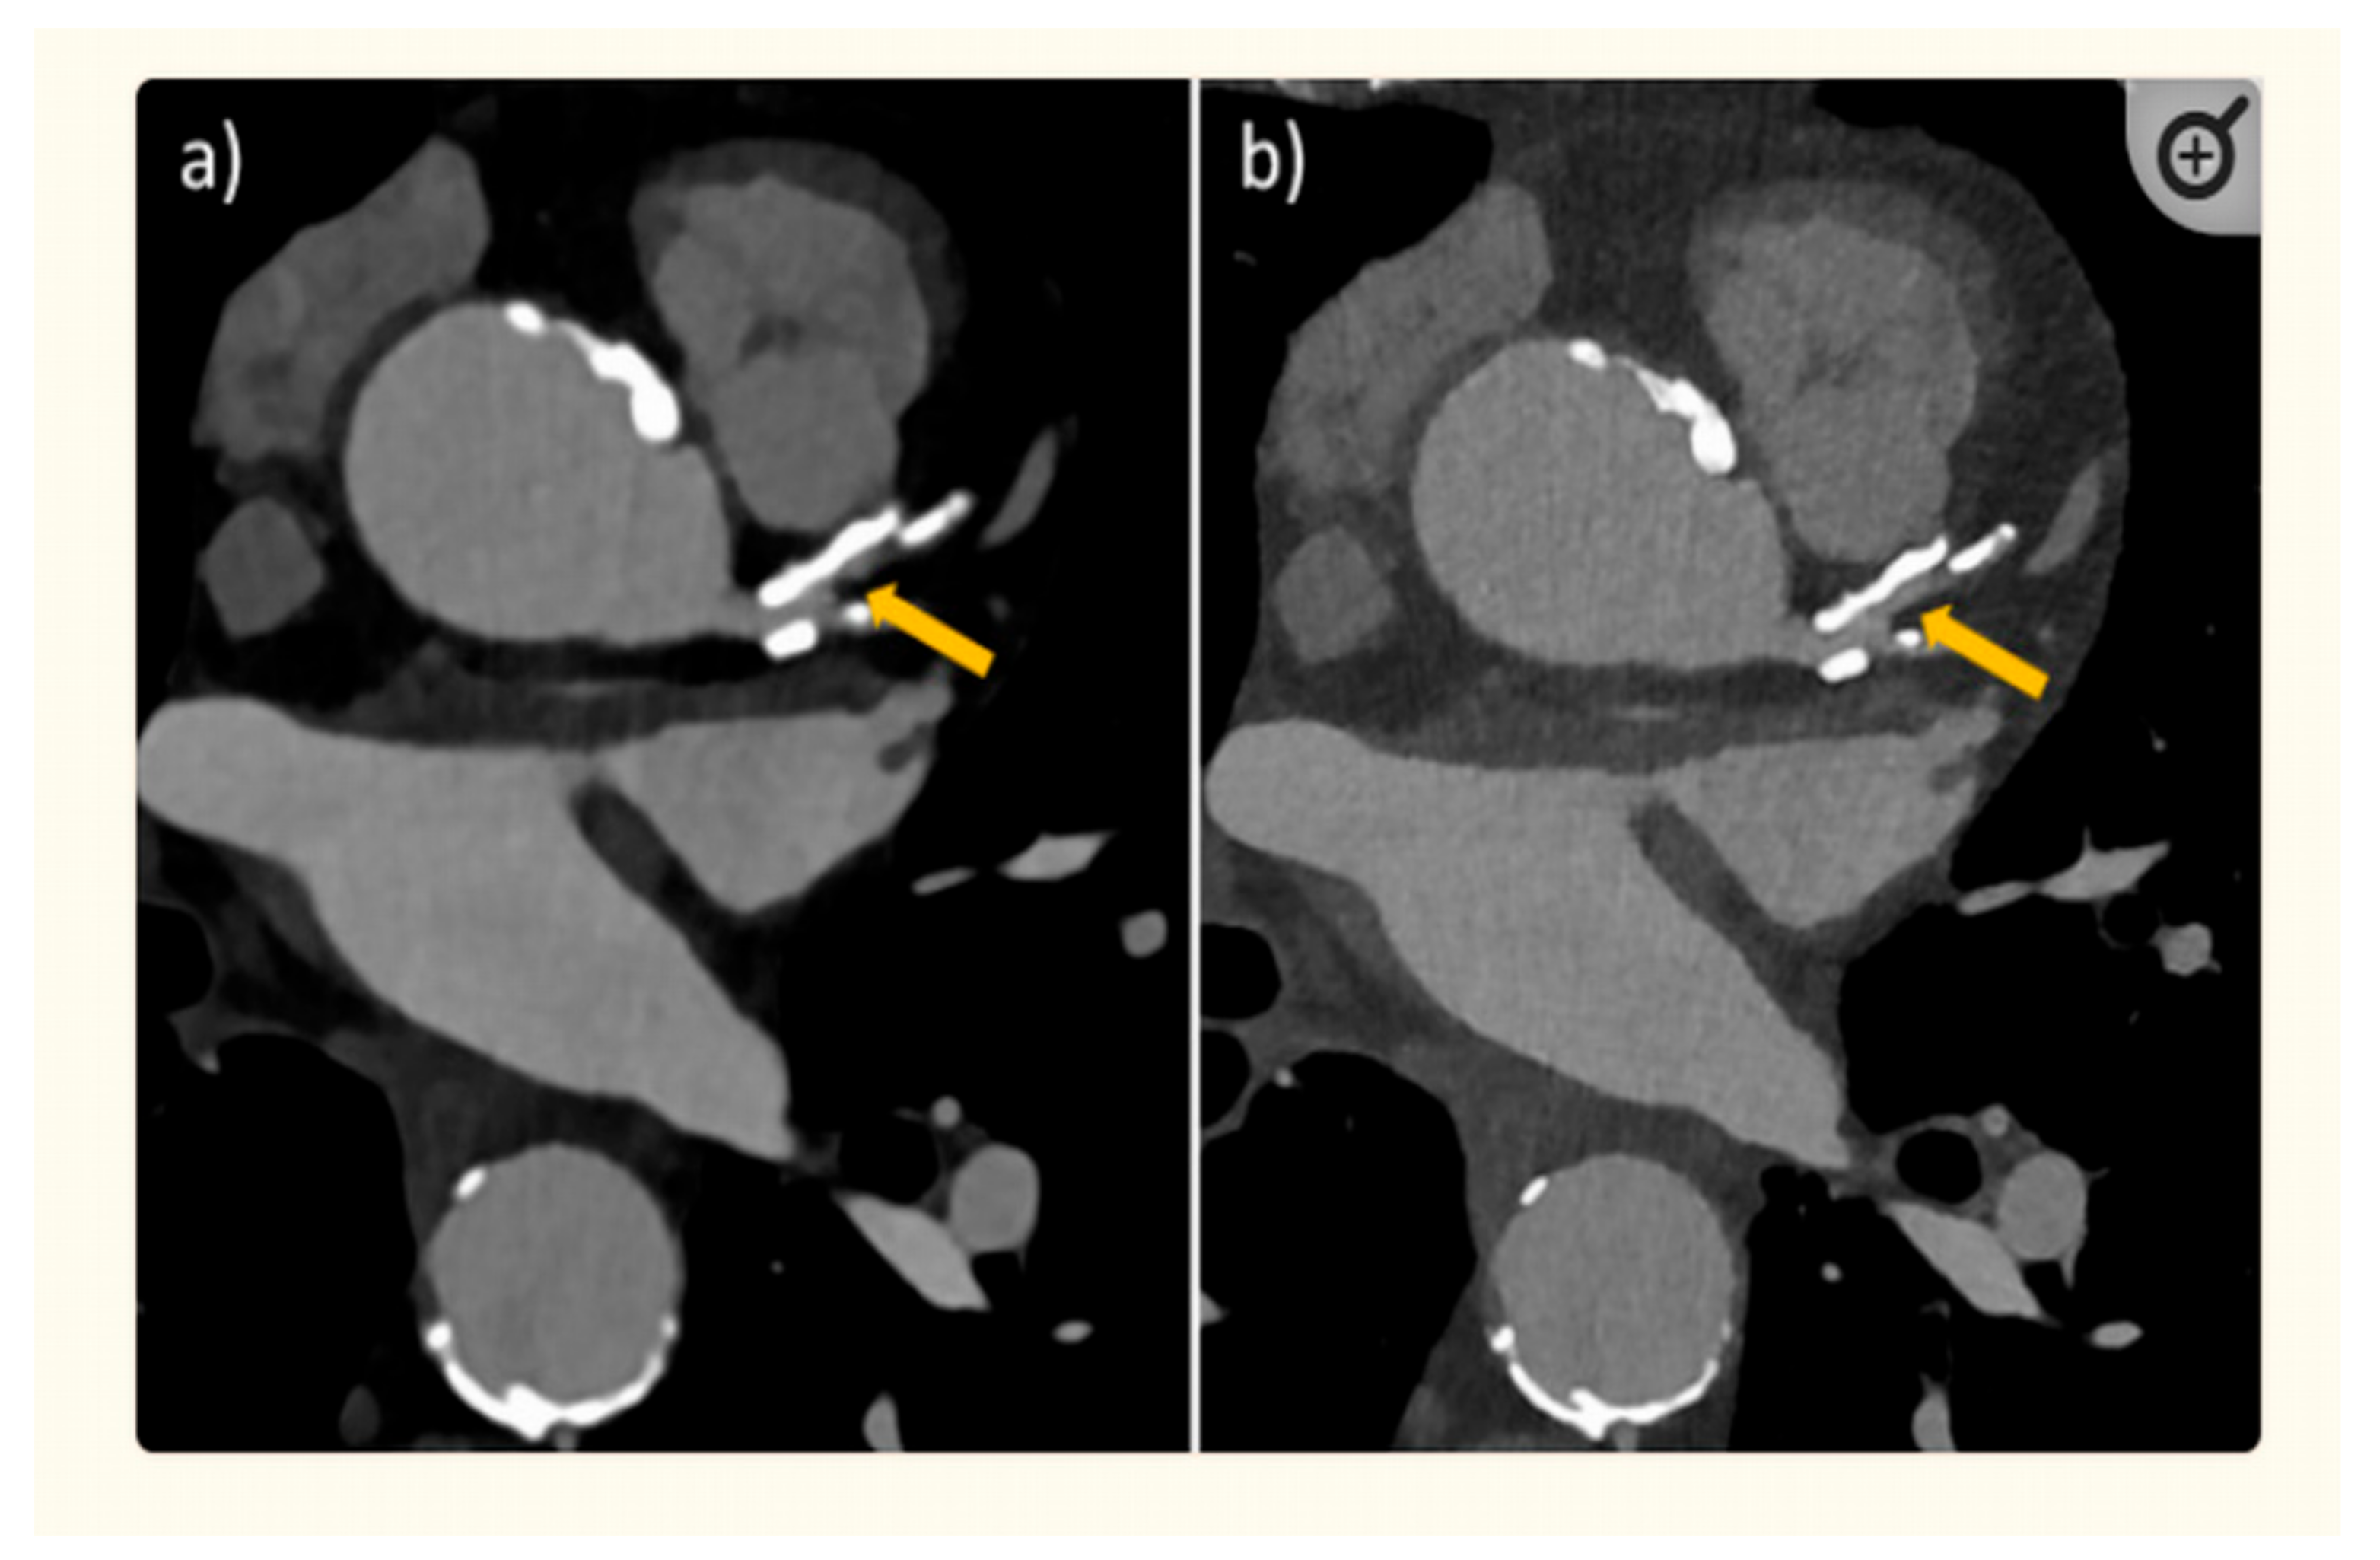

- Boccalini, S.; Si-Mohamed, S.A.; Lacombe, H.; Diaw, A.; Varasteh, M.; Rodesch, P.A.; Villien, M.; Sigovan, M.; Dessouky, R.; Coulon, P.; et al. First in-Human Results of Computed Tomography Angiography for Coronary Stent Assessment with a Spectral Photon Counting Computed Tomography. Investig. Radiol. 2022, 57, 212–221. [Google Scholar] [CrossRef] [PubMed]